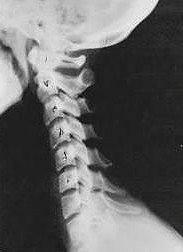

Near Normal

This is a side x-ray view of the neck.  As with all the pictures you will see on this page, the patient is looking to the left of the screen, so you are viewing the left side of their neck.  We will call this picture a “near normal” spine.  Compare this spine with the ones you will see below on this page.  Notice the normal forward curve of the neck.  This curve helps absorb shock.  Notice how each of the disc spaces between C2 (second bone in neck) and C7 are thick and even, this again is normal.  Also notice how the front portions (right on the x-ray) of each of the vertebrae (called the ‘body’ of the vertebrae) are fairly square with clear and well defined borders. This type of arrangement is normal in the neck.  Normal vertebrae in other parts of the spine also have similar characteristics to what we see here. When subluxations occur and are left uncorrected, ongoing relentless changes occur that result in damage to the structure and function of the spine along with nerve damage and the resulting problems caused from improper nerve supply.